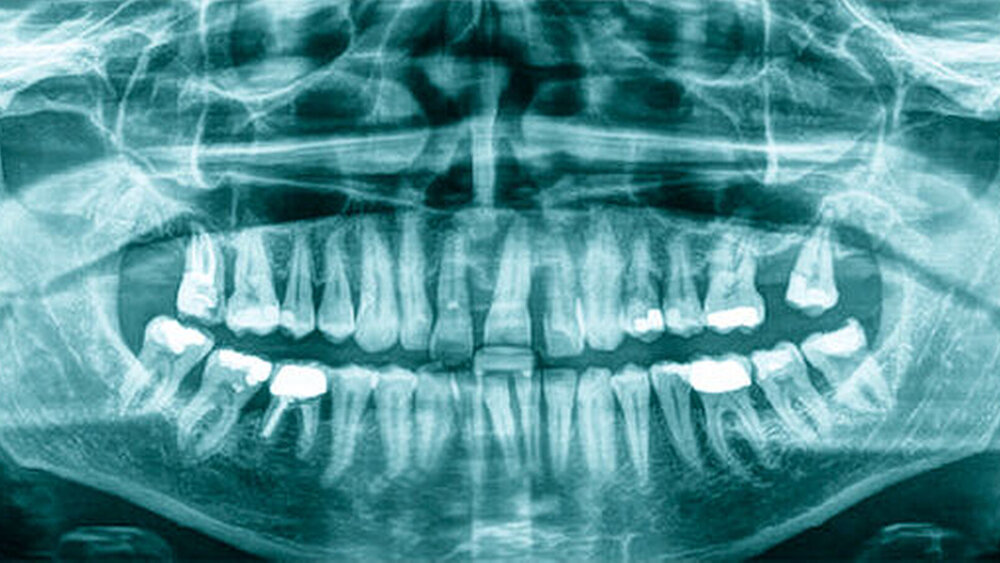

Röntgenologisch stellte sich im Orthopantomogramm der bereits intraoral ersichtliche horizontale und vertikale Knochenabbau mit Attachmentverlust an einzelnen Zähnen dar. Die Erhaltungswürdigkeit einzelner Zähne war aufgrund des starken Knochenverlustes beziehungsweise der Beeinträchtigung des Halteapparates als kritisch zu beurteilen.

Zudem wurde die Diagnose einer Parodontitis gestellt, die eine Rücküberweisung an den Hauszahnarzt erforderlich machte (Abbildung 2).